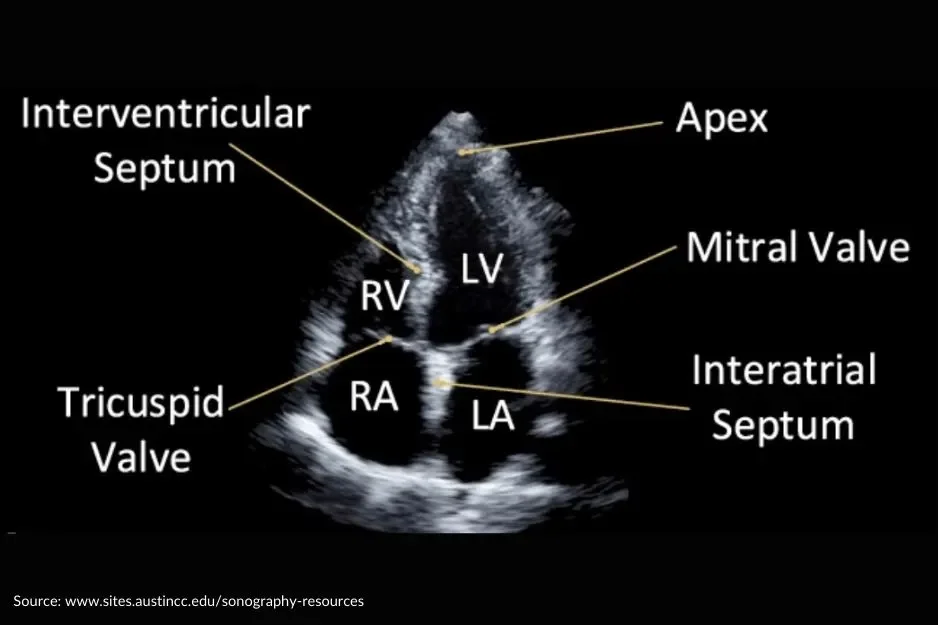

Welcome to our Echocardiography learning platform, where we are aim to help you learn & develop your echocardiography skills from home.